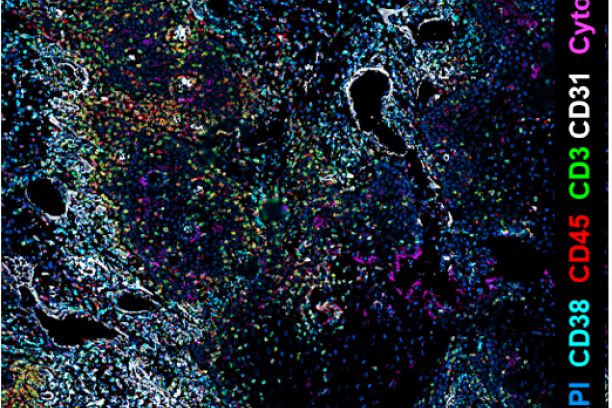

We are so excited to offer the PhenoCycler (formerly CODEX) as a new core service through the Innovative Translational Shared Resource at the Vanderbilt Ingram Cancer Center! The CODEX is a highly multiplexed immunofluorescence system that provides spatial characterization of the tissue microenvironment at the single cell level and uses single step staining to preserve tissue integrity and an automated process of imaging biomarkers using the PhenoCycler instrument and Keyence BZ-X 810 microscope.